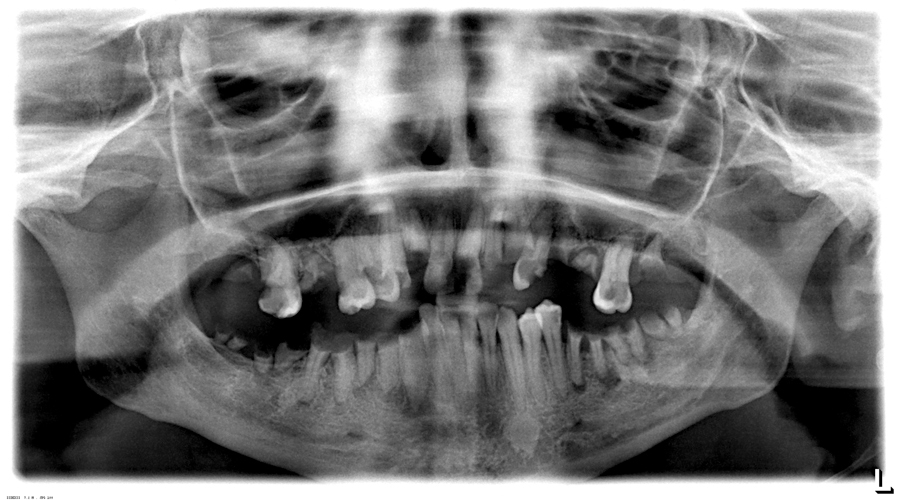

Millar Image5 alternate text for this image

Introduction Alcohol and drug dependence is an ongoing worldwide problem. The effects of alcohol kill 3.3 million people every year. This amounts to 5.9% of all deaths.1 Alcoholic liver disease is at an all time high level, and alcohol is now the third leading cause of ill health after tobacco and high blood pressure in … Read more